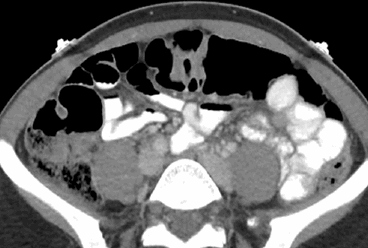

Органы брюшной полости, ретроперитонеального пространства. КТ живота является точным методом для диагностики абдоминальных патологий:

Процедура предпочтительна для выявления причин острой боли в животе, пояснице. К таковым относят:

нефролитиаз, закупорку мочеточника кровяным сгустком, белковой пробкой;

аневризма брюшной аорты

инфаркт, разрывы селезенки и пр.